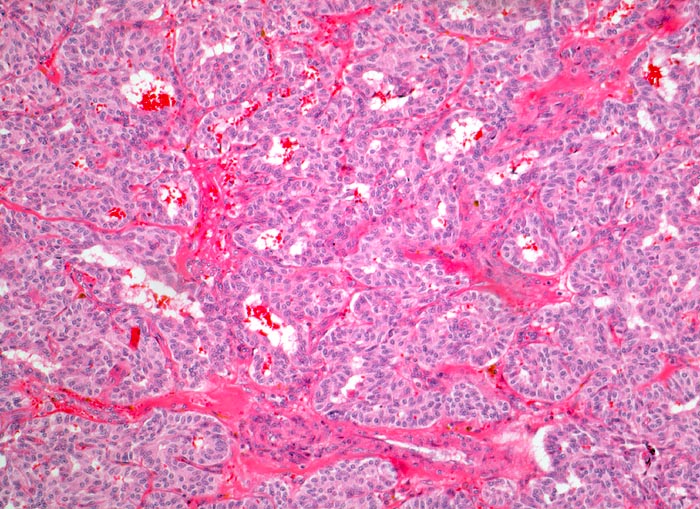

medulläres Schilddrüsenkarzinom

Aus polygonalen und spindeligen Tumorzellen aufgebauter teils trabekulärer, teils alveolärer Tumor. Dazwischen schmale Bindegewebssepten.

Graubrauner teils unscharf begrenzter Knoten in der Schilddrüse. Tumorzellen CEA und Calcitonin positiv.

jeder morphologisch ungewöhnlich aussehende Schilddrüsentumor sollte immunhistochemisch untersucht werden mit Antikörpern gegen Calcitonin, CEA und Thyreoglobulin.